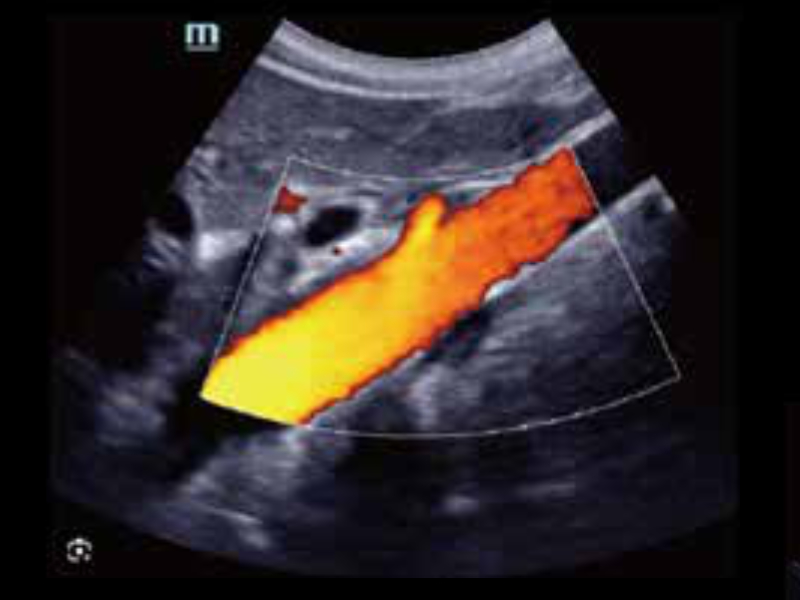

Ultrasonografia kończyn dolnych – duplex

• zeus-fig5-3-4-uk

Aorta

Przetworniki